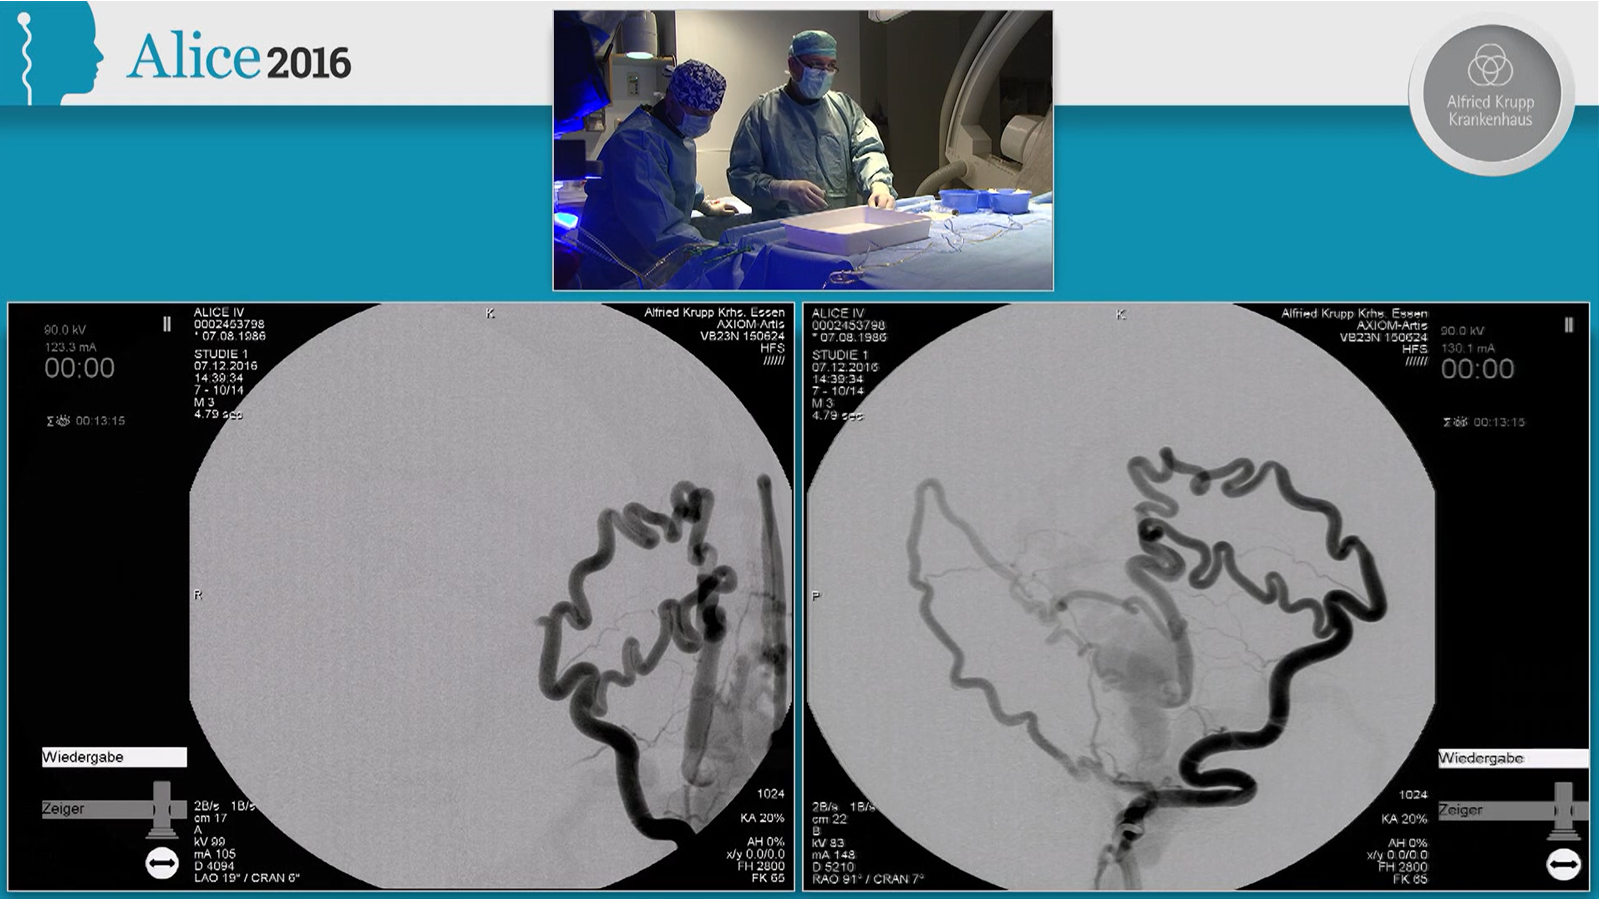

MCA aneurysm treated by double balloon assisted coiling followed by Stenting with Baby Leo

MCA aneurysm treated by double balloon assisted coiling followed by stenting with Baby Leo through Scepter XC

MCA Aneurysm treated by double balloon assisted coiling and Stenting with Baby Leo